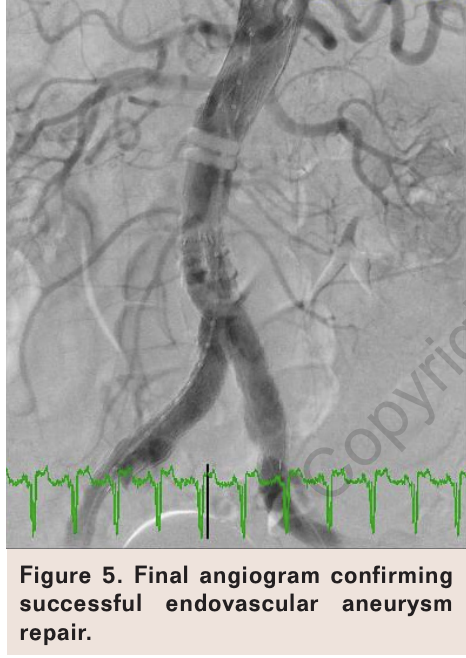

The device was positioned using multiple contrast injections via the left femoral artery immediately below the renal arteries. After final confirmation of the graft position, the aortic body was completely released and the polymer mixed and infused to fixate the device (Figure 4). The contralateral limb was cannulated and wired via the left femoral sheath, and a 14 Fr Ovation 16 mm x 120 mm extension limb was deployed. An Ovation 22 x 140 mm extension limb was then deployed in the ipsilateral side and the proximal, mid, and distal body post-dilated using a compliant Reliant balloon (Medtronic). A final aortogram confirmed an excellent angiographic result with apposition of the graft in the aortic and iliac segments and no evidence of endovascular leak (Figure 5).